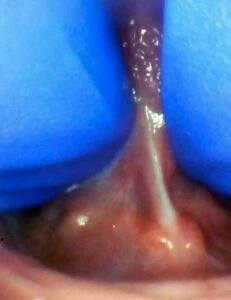

IMAGES OF TONGUE- AND LIP-TIES

Spectrum of tongue restriction in an infant